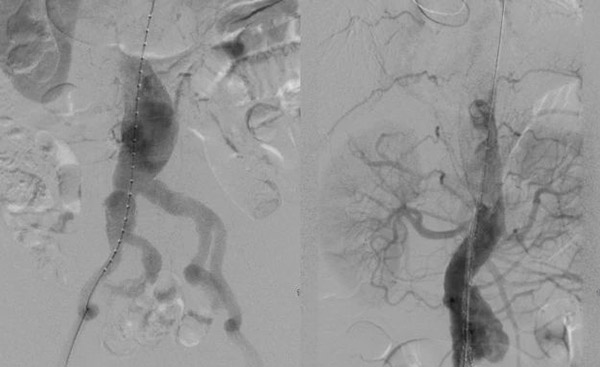

手术当天,肿瘤介入团队为患者实施腹主动脉-双侧髂动脉覆膜支架置入术。术中精准地将支架分别置入腹主动脉和左侧髂总动脉、右侧髂总及髂内动脉。成功将动脉瘤与血管腔分离,达到腔内隔绝的同时,也避免了分支血管缺血。实现了所有分支动脉完整保留,无任何并发症的目标。历时3.0个小时,微创手术取得成功,DSA显示动脉假腔完全消失,血管恢复正常形态,达到预期目的。术后患者各项指标均恢复良好,并已康复出院。 术前造影以及确定肾动脉、主要血管位置 主动脉支架手术:血管内的神奇“修补匠” 主动脉支架释放 髂内动脉支架释放 球囊扩张确保支架完全释放 手术前后对比———术后DSA显示假腔消失,腹主动脉血管恢复正常形态 此次手术的成功开展,为沈阳十院在大血管疾病介入治疗方面的进一步发展奠定了基础,也为未来类似病例的治疗提供了宝贵的经验。沈阳市第十人民医院肿瘤介入科开展了多种疾病的介入治疗。在血管疾病方面再上新高,开展主动脉夹层、主动脉瘤、下肢动脉硬化、下肢深静脉血栓等疾病的介入治疗。在实体肿瘤方面突破进取,开展肺、肝脏、胰腺、胆囊等恶性肿瘤微创介入诊疗技术。在危重症领域上持之以恒,开展咯血、肺栓塞、消化道呕血等疾病的介入治疗。未来,肿瘤介入科团队,将继续致力于技术的创新与推广,为更多患者带来生命的福音和健康的保障。